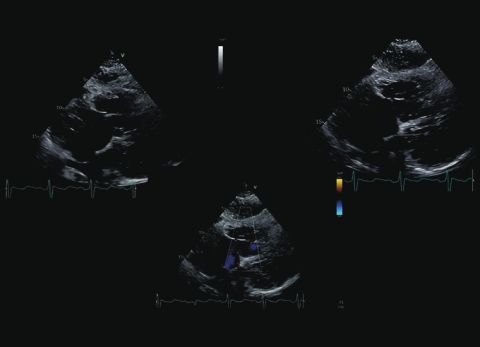

Wideo Echokardiografia. Przypadek 11

prof. dr hab. n. med. Zbigniew GąsiorPacjentka z narastającą od miesięcy dusznością wysiłkową (klasa NYHA III); przewlekła choroba nerek, nadciśnienie tętnicze.